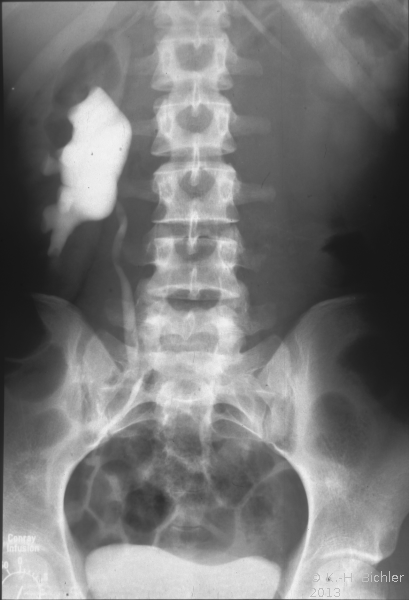

• Abbildung 17: Ureterabgangsstenose mit ausgedehnter Hydronephrose links

1. Ausscheidungsurogramm stumme Niere links (schwacher nephrographischer Effekt)

2. Spätaufnahme (AUR): Erheblich dilatiertes Nierenbecken links